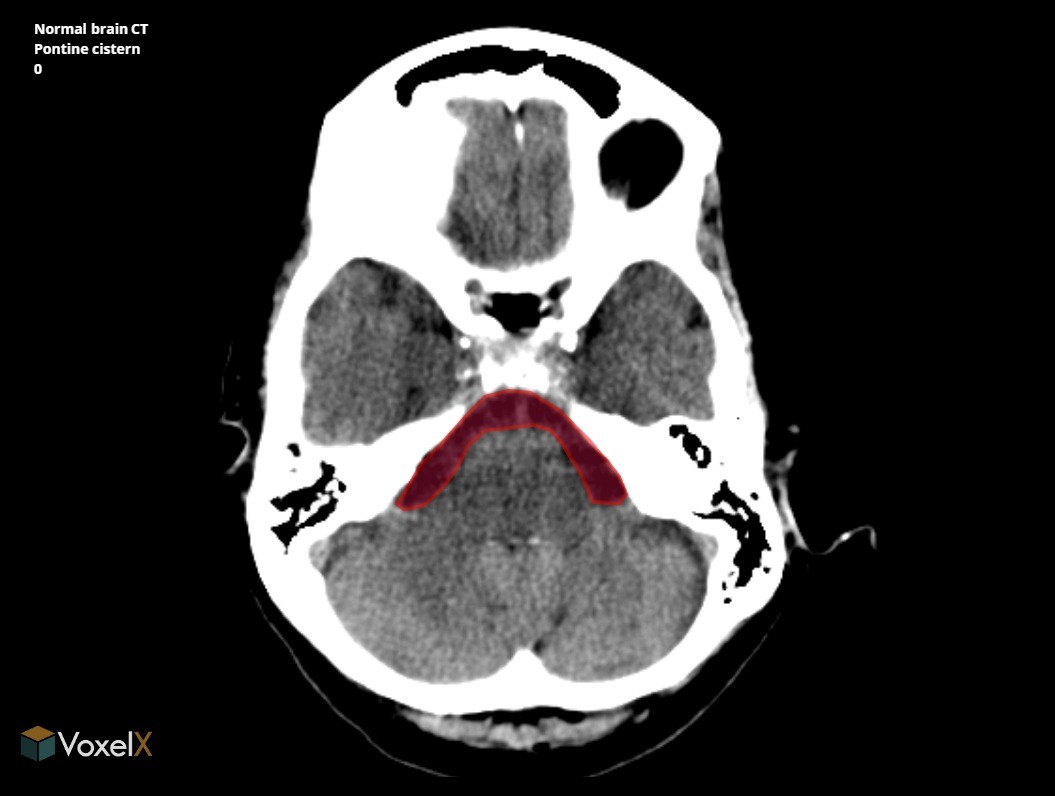

What is the name of the dilatated subarachnoid space into which foramen luschke open?

(Cerebello)Pontine cistern